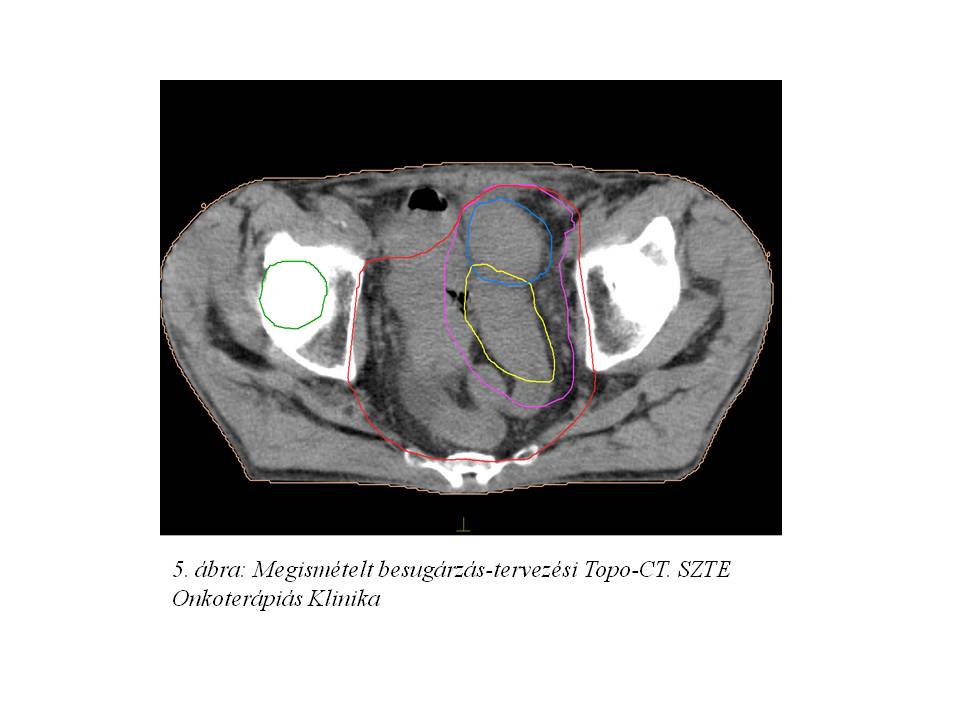

Opust követően az aktív onkológiai kezelés 2014 júliusában indult újra. A megismételt besugárzás-tervezési topo-CT (5. ábra, 6. ábra) mérsékelt tumoros regressziót igazolt. A beteg sugárkezelését további 17x1,8 Gy + a residualis makroszkópos tumornak megfelelően szűkített célterületre további 5x1,8 Gy összdózissal komplettáltuk, az 1. és 5. héten iv. 5FU+Leucovorin kemoterápiával kombinálva, tekintettel a korábbi compliance problémákra.